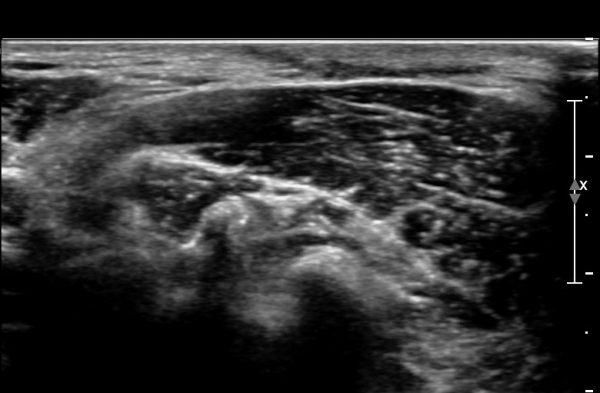

ŽÃÊÀÚ¸¦ ¾à°£ ¸»´ÜÀ¸·Î À̵¿ÇÏ´Ï ¼ö¼ú ¹ÝÈçÀÌ °üÂûµÇ°í  ¼ö¼ú¹ÝÈç ÈÄ¹æ ½ÉºÎ¿¡¼­

ôÃߺνŰæÀÌ °üÂûµÇ´Âµ¥ ½Å°æÀÇ ¿¬¼Ó¼ºÀº À¯ÁöµÇ¾î ÀÖ´Ù(»çÁø 4, 5).